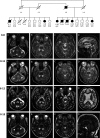

Objective: Mitochondrial dysfunction plays a key role in the pathophysiology of neurodegenerative disorders such as ataxia and Parkinson's disease. We describe an extended Belgian pedigree where seven individuals presented with adult-onset cerebellar ataxia, axonal peripheral ataxic neuropathy, and tremor, in variable combination with parkinsonism, seizures, cognitive decline, and ophthalmoplegia. We sought to identify the underlying molecular etiology and characterize the mitochondrial pathophysiology of this neurological syndrome.

Methods: Clinical, neurophysiological, and neuroradiological evaluations were conducted. Patient muscle and cultured fibroblasts underwent extensive analyses to assess mitochondrial function. Genetic studies including genome-wide sequencing were conducted.

Results: Hallmarks of mitochondrial dysfunction were present in patients' tissues including ultrastructural anomalies of mitochondria, mosaic cytochrome c oxidase deficiency, and multiple mtDNA deletions. We identified a splice acceptor variant in POLG2, c.970-1G>C, segregating with disease in this family and associated with a concomitant decrease in levels of POLG2 protein in patient cells.